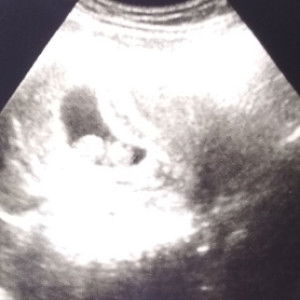

semenjak usia kehamilan ku memasuki 20week . tendangan2 halusnya udah mulai terasa ..awallnya blom trus memasuki 20w1d kerasa bgt ..yaallah seneng bgt . ada yg sama ga bund ....

iya bun, saya skrg sdh 22 tendangan nya makin berasa bun